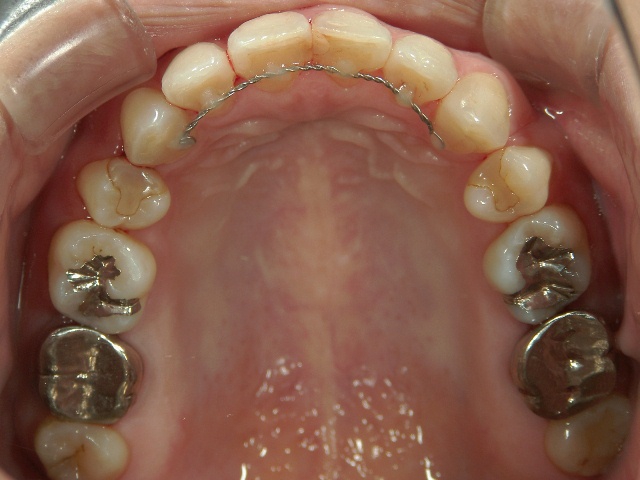

矯正歯科(全顎ワイヤー矯正)治療後

36歳女性 磐田市

在住

治療期間2年6

ヶ月